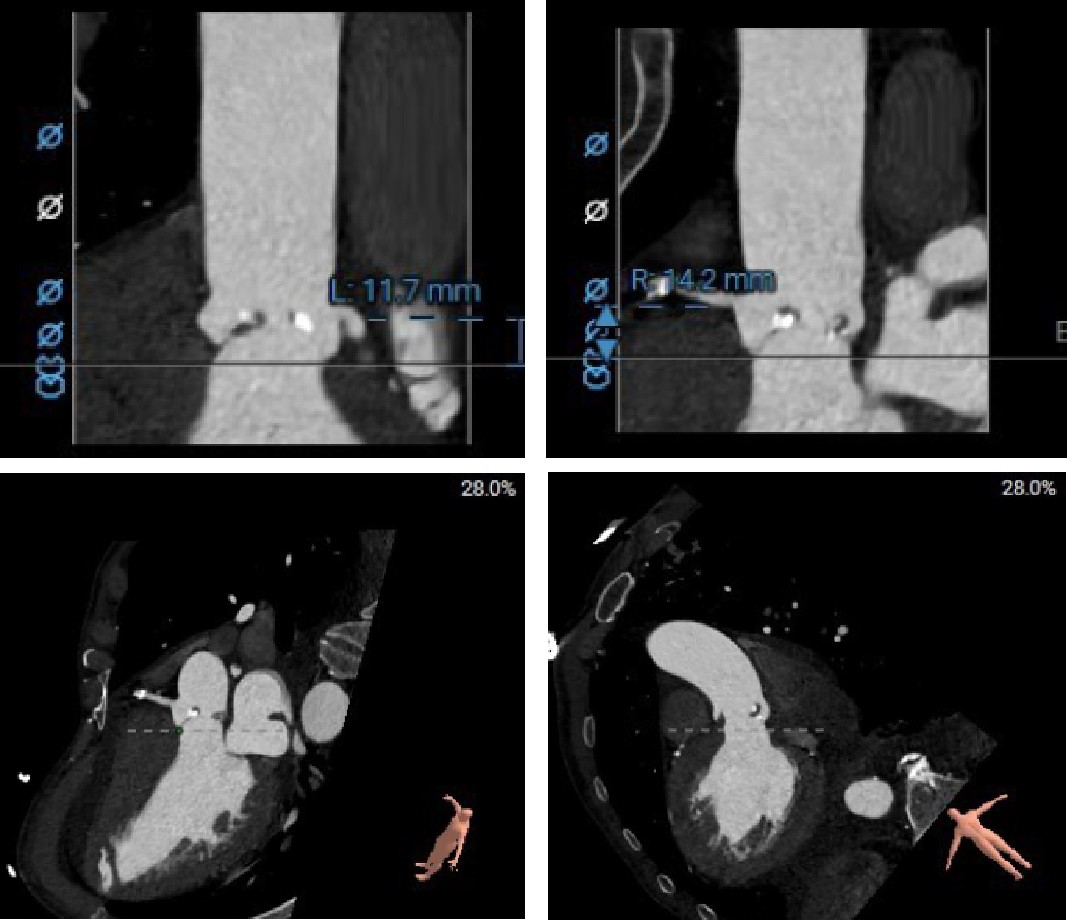

范嘉祺教授就CT在TAVR术前评估及手术策略制定展开了深入讲解。TAVR术前CT评估主要包括:1、入路血管的评估选择入路方式;2、主动脉根部解剖的评估制定球囊、瓣膜选择策略;3、心室大小、冠状动脉阻挡风险等。4、相比西方国家,我国二叶瓣比较高,且产生严重钙化的比例也较高,以往根据瓣环选择瓣膜的策略可能带来风险。故针对国内患者的情况,需要术前更加精细的瓣上结构分析,并结合术中球扩,优化瓣膜选择策略,提高手术的安全性和有效性。

精彩的理论授课外,王建安教授团队通过一例复杂的TAVR手术演示,全面展示了Hangzhou Solution在评估瓣上结构,指导二叶瓣TAVR手术策略的应用,以及可回收系统在复杂病变中给临床带来的获益。

主动脉根部

冠脉及心室